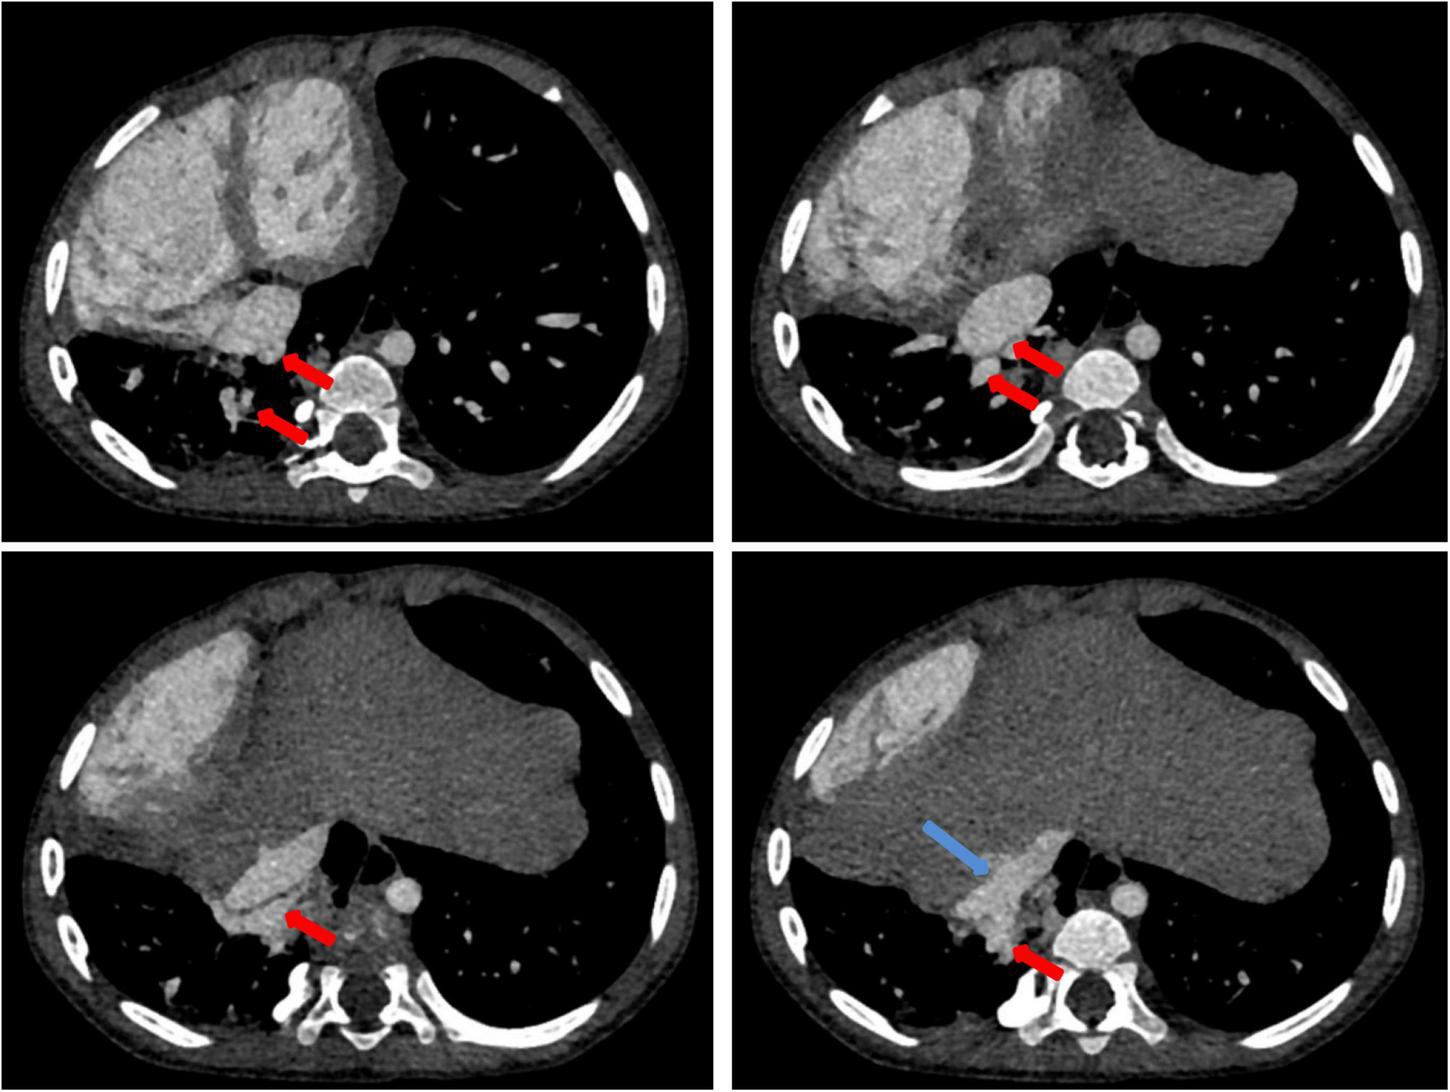

Chest X-ray showed a large area of high density in the lower right lung. Chest CT showed a 9 mm defect in the atrial septum (Figure 1A), a significantly small right pulmonary artery (∼5 mm) and a significantly small right superior pulmonary vein (Figures 1B–D), a small and sparsely branched right lung, and the venous of sequestration lung return to the hepatic vein (Figure 2). Considering the patient’s young age and inability to tolerate cardiac and pulmonary surgery, isolated pulmonary embolism and atrial septal occlusion were performed under general anesthesia. Digital subtraction angiography (DSA) and CT 3D reconstruction (Supplementary Video) showed an abnormal blood vessel branching from the right renal artery opening (∼4 mm; Figures 3A–C), and arching toward the right lower lung for blood supply. During the operation, nine coils of equal size were applied to completely block the abnormal blood supply to the right lower lung. Under transthoracic ultrasound guidance, a 14 mm atrial septal occluder was placed through the delivery sheath and ascertained to be adequately fixed, with no residual shunt and intact valvular apparatus (Figure 3D).

FIGURE 2

Contrast-enhanced CT of the chest: contrast-enhanced CT shows the isolated pulmonary venous draining (red arrow) into the hepatic vein (blue arrow).